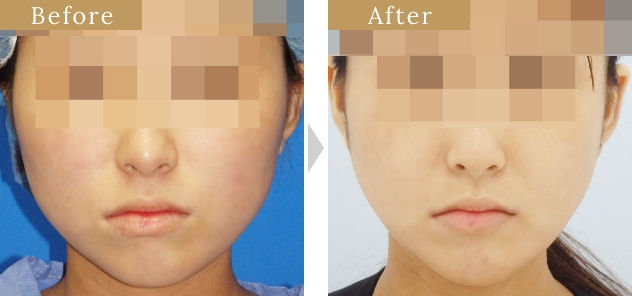

症例